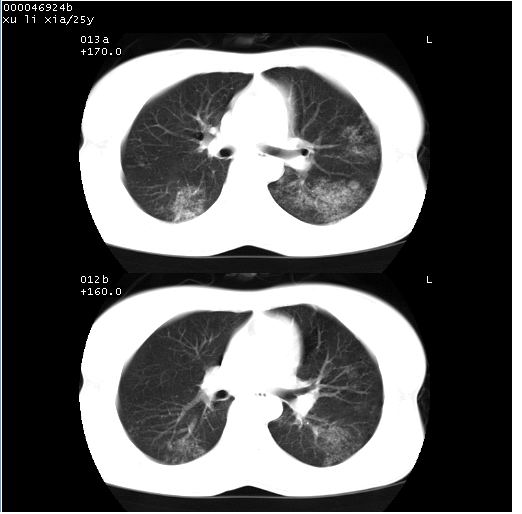

患者 女,25岁。因“左侧卵巢肿瘤”术前胸片偶然发现两肺病变。平素无明显不适,无呼吸系统症状及体征,无传染病史。

cr x线胸片提示:两肺感染性病变(结核可能性大)。

胸部ct轴位平扫(层厚10mm,螺距1.5,重建间隔10mm),图像如下:

(注:上级医院会诊胸部ct片——考虑为肺部真菌感染。)

病灶呈地图样分布于肺外围,与正常组织分界清晰+弥漫性磨玻璃影中见小叶间隔增厚呈碎石路样表现+年轻女性,无明显临床症状=肺泡蛋白沉积症?

双肺上叶可见节段性渗出性病变,可见树芽征像,左肺下叶背段可见结节影。

病灶呈离心性分布,以两上肺多见,远离肺血管纹理,有部分肺间质条索影,病人症状轻微,考虑结节病。